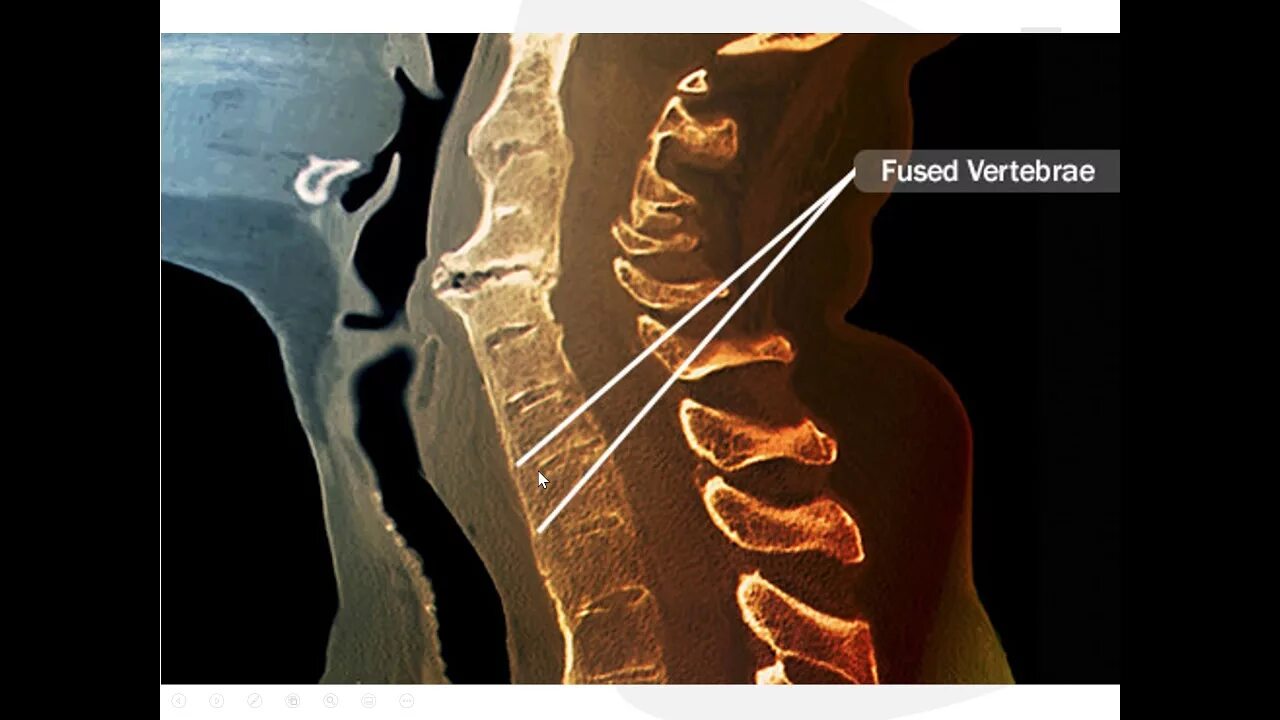

Спондилоартроз кт